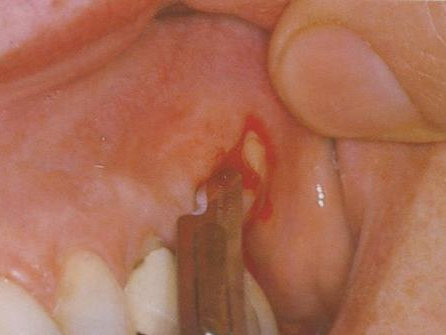

由于口腔诊疗一般都会造成患者口腔黏膜和皮肤损伤,80%~90%的患者在洗牙或补牙时会出现牙龈出血等问题。这意味着,如果前一个洗牙、补牙患者患有乙肝等传染性疾病,而他治疗所用的机头、器具没有经过彻底的消毒处理,或使医生的手被污染了, 那么乙肝病毒等就可能通过机头、器具、医生的手等传播给下一个患者。